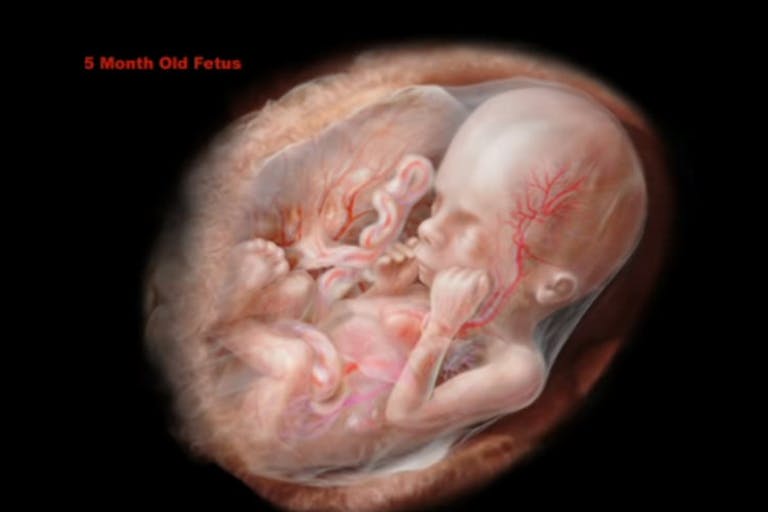

A bill banning abortions beyond 20 weeks has passed the Mississippi House and now makes its way to the Senate, offering hope for life for Mississippi babies aborted even beyond viability.

Of the almost 2,200 abortions in Mississippi in its last reported year, only two were listed as being beyond 21 weeks, but the ban would ensure that these late-term abortions are prevented.